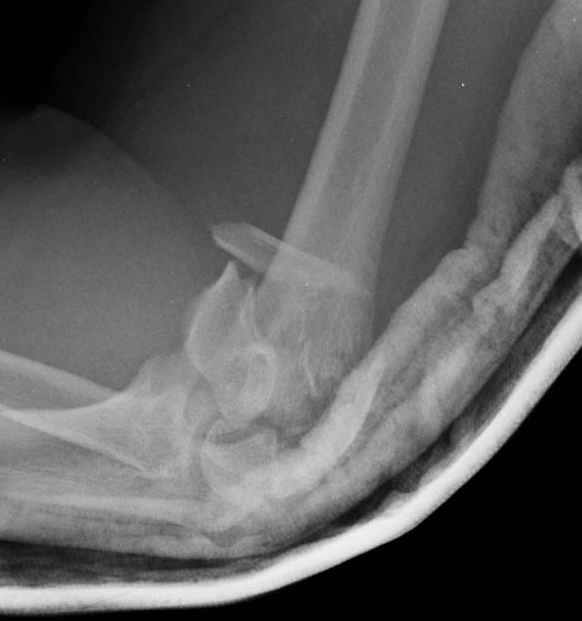

Уважаемые коллеги! Мужчина, 28 лет. 1 сутки назад получил бытовую травму - закрытый чрезмыщелковый перелом правой плечевой кости со смещением. По месту жительства в ЦРБ - репозиция, иммобилизация. Направлен к нам.

Солидарен с мнением обоих Александров (Челнокова и Рыкова): точную репозицию такого перелома вряд ли удастся выполнить закрыто. Даже во время открытого вмешательства это сделать непросто. Неслучайно предложен костно-пластический доступ с временным отсечением локтевого отростка. И по методу фиксации согласен с Александром Челноковым: 2 пластины. В качестве примера привожу рентгенограммы одного из наших пациентов с аналогичным повреждением.

С уважением, А. Золотов, Приморский край.